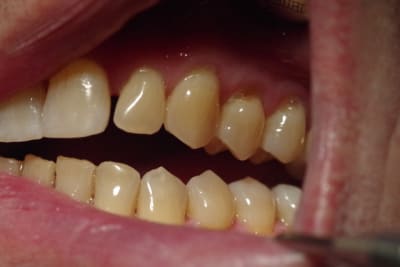

Les photos sont assez évocatrices car le plan de Fox mis à l'arcade supérieure montre nettement une divergence entre la ligne bipupillaire et le plan.

J'ai pris aussi une photo en demandant au patient de déglutir et on voit la langue qui s'interpose entre les arcades ( là où il y a béance).

Ce monsieur a une langue très présente (photo 2) => rééducation.

La photo avec la langue a été prise au moment où j’ai demandé au patient de déglutir : le test a été révélateur car ce patient a une déglutition infantile ou primaire ( je ne connais pas très bien les termes) et pousse sa langue sur les dents.